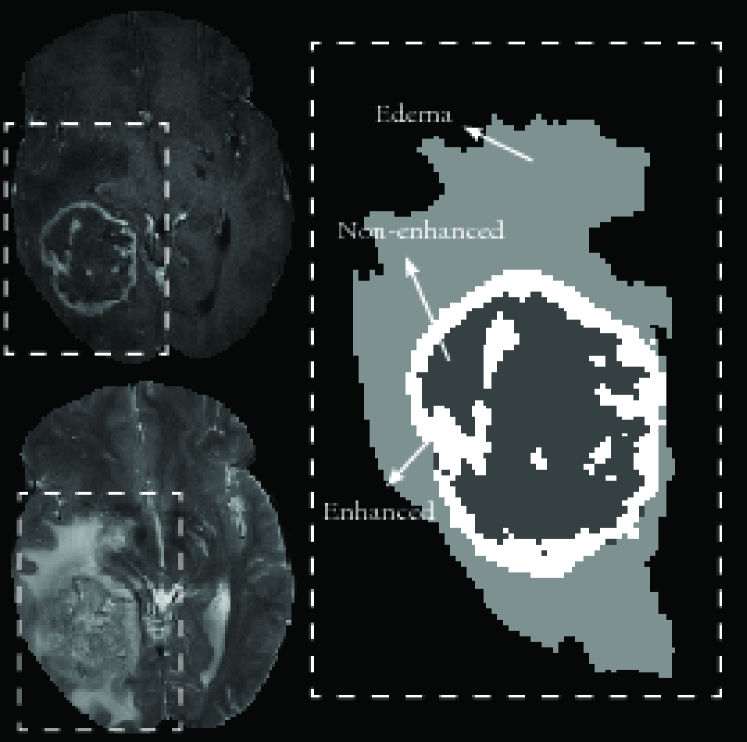

Brain tumor segmentation is primarily used for diagnosis, patient monitoring, treatment planning, neurosurgery planning and radiotherapy planning. The task of brain tumor segmentation is to locate the tumor and delineate different sub-regions of the tumor, namely edema, non-enhanced, and enhanced regions (see Fig. 1). A standard way to diagnose a brain tumor is by using magnetic resonance imaging (MRI), for which many different modalities can be used. The most frequent MRI modalities used for brain tumor segmentation are Flair, T1-weighted (also referred to as T1), T2- weighted (also referred to as T2) and T1-weighted contrast-enhanced (gadolinium-DTPA) which we refer to as T1C. These different modalities are often used jointly as they provide complementary information for locating tumors.

Refer to caption

Figure 1: Left: T1C and T2 modality. Right: groundtruth tumor segmentation.

In this paper, we consider the specific problem of segmenting an imaged brain into 4 classes: edema, non-enhancing tumor, enhancing tumor and healthy tissue (see Fig. 1). Note that the non-enhancing tumor sometimes includes necrotic tissue. Our approach is halfway between automatic and semi-automatic methods. While machine learning methods train on a pre-selected set of brains and then generalize to testing brains, our method implements a “single brain” supervised learning method. The user roughly selects brain voxels associated to each class and then these voxels are used as training data. The method then generalizes by labeling non-selected voxels.